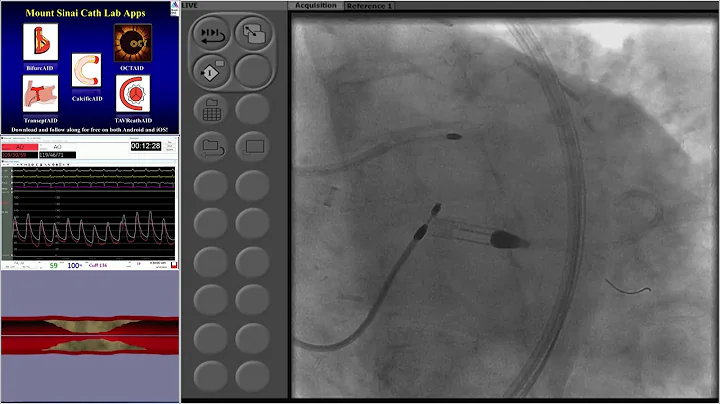

Expanded Indications Of Impella: Protected Pci - Dr. Lasala